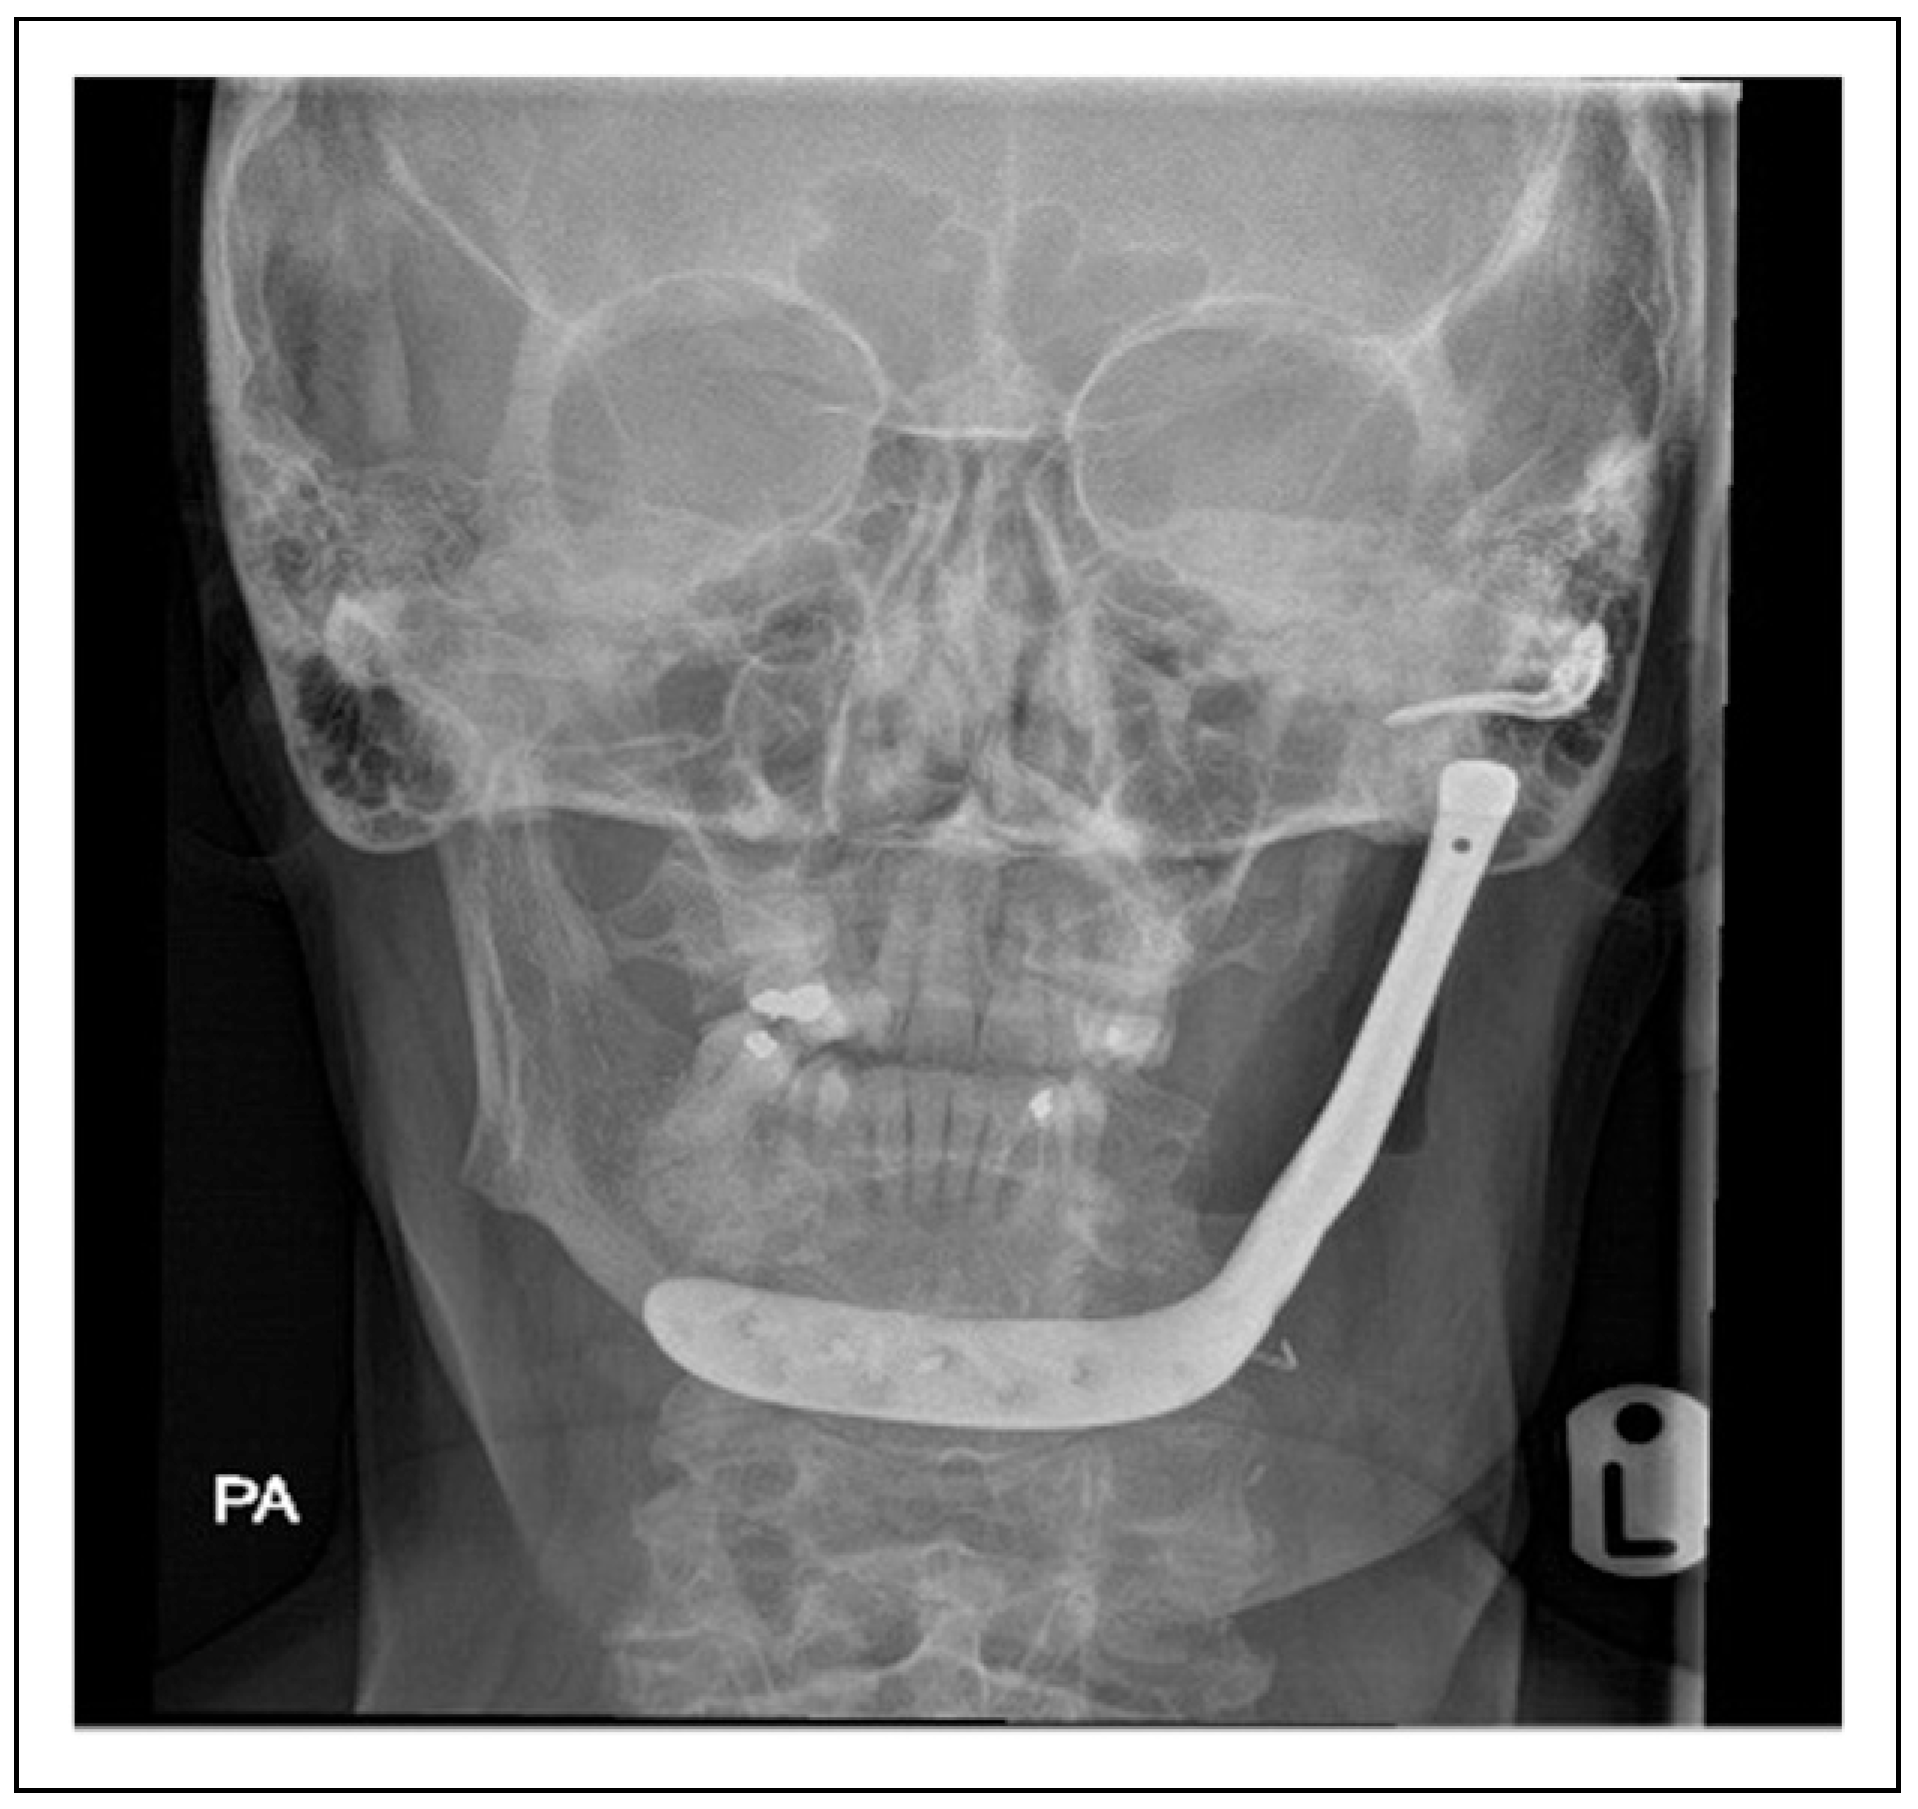

Single-Stage Regime, Patient 10